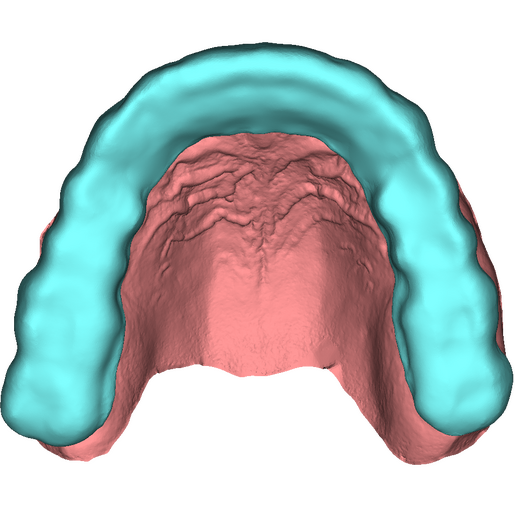

DSD Bite Splint Design

The DSD Bite Splint (night guard) is designed to be worn after a full mouth rehabilitation to protect DSD Natural Restorations and/or DSD Direct composite restorations. The splint design can be used for both milling and printing.

This product is ideal when you need to protect restorations that have already been placed to help avoid possible fractures due to grinding and bruxism.

This is a digital product, delivered in STL format.

An .STL file of the DSD Bite Splint design that can be used for manufacture, either by DSD Lab or your local lab.